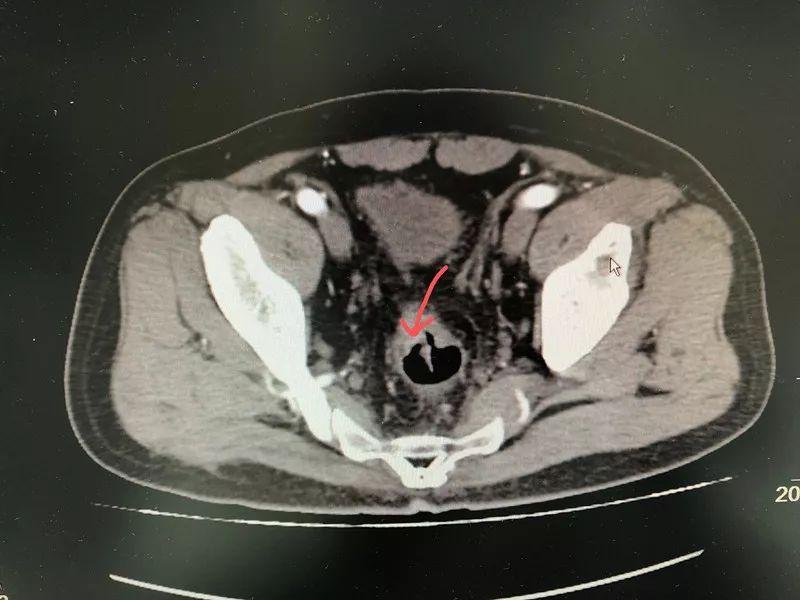

肠镜检查发现,直肠上长出新生物,经活检检验为直肠腺癌。